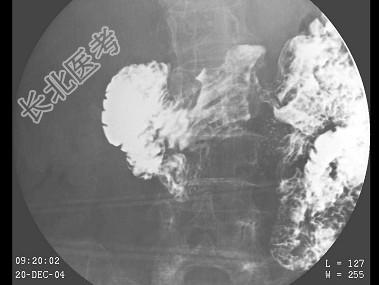

- 35岁,男, 结合图像,最可能的诊断是